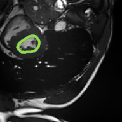

Despite their outstanding accuracy, semi-supervised segmentation methods based on deep neural networks can still yield predictions that are considered anatomically impossible by clinicians, for instance, containing holes or disconnected regions. To solve this problem, we present a Context-aware Virtual Adversarial Training (CaVAT) method for generating anatomically plausible segmentation. Unlike approaches focusing solely on accuracy, our method also considers complex topological constraints like connectivity which cannot be easily modeled in a differentiable loss function. We use adversarial training to generate examples violating the constraints, so the network can learn to avoid making such incorrect predictions on new examples, and employ the Reinforce algorithm to handle non-differentiable segmentation constraints. The proposed method offers a generic and efficient way to add any constraint on top of any segmentation network. Experiments on two clinically-relevant datasets show our method to produce segmentations that are both accurate and anatomically-plausible in terms of region connectivity.